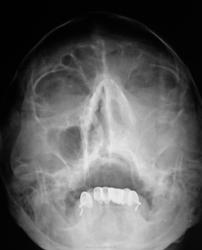

похоже на гиперпластический. В лобной пазухе виден уровень жидкости.

А я плохо вижу костные стенки левой гайм. пазухи...."оно" проростает..

Согласен, невиден медиальный контур левой гайморовой пазухи, надо исключить деструкцию

затемнение не совсем гомогенное, возможно солидные образования в верхнечелюстной пазухе. Во фронтальной не вижу достоверных данных за уровень-что можно было бы трактовать за жидкость. Для этого надо уточнить положение пациента при исследовании, а так же рентгенография пазух лобной кости в боковой проекции в вертикальном положении пациента. Имея только этот снимок - Левостороний гемисинусит. А вообще рекомендовал бы томографию, ну честно-все встало бы на места.

Снимок сделан в вертикальном положении.